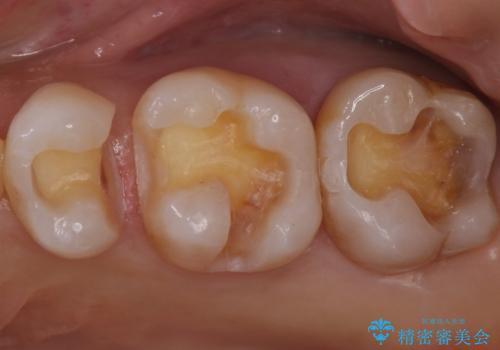

- 銀歯を白くしたいとのことで来院されました。

特に大きな虫歯もなかったため、周りの歯を残しつつセラミックインレーでの修復処置をしていきます。

大きな虫歯さえなければ、銀歯のやり替えは詰め物の周りの歯を保存しつつ修復することができます。